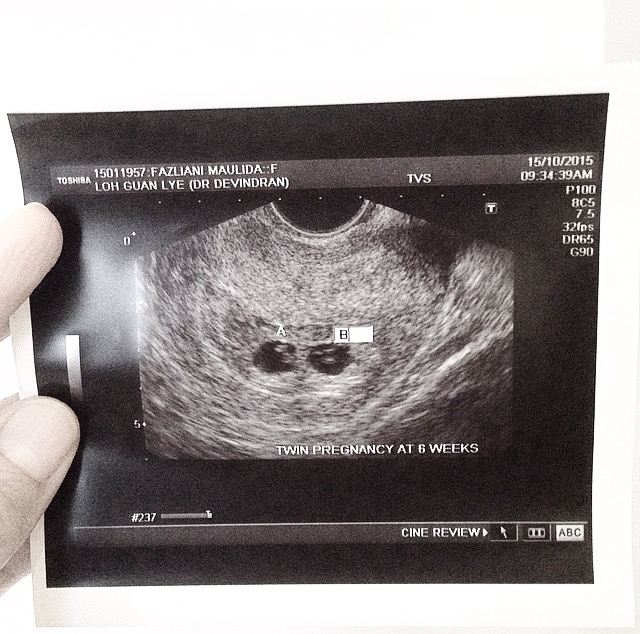

Lalu saya pun kembali ke klinik Dr. Dev 2 minggu setelah pengecekan pertama. Kali ini saya berangkat bersama dengan kakak ipar yang juga kebetulan ingin berkonsultasi dengan Dr. Dev. Awalnya saya agak khawatir karena Ibu dan suami yang tidak ikutan. Bagaimana kalau nanti menerima kabar buruk lalu tidak ada mereka yang menenangkan saya. Lagi-lagi pikiran buruk yang menghantui. Namun saya coba berpikir positif kalau janin yang ada dalam kandungan saya dalam keadaan sehat tidak kurang suatu apapun. Kedatangan kali ini tidak ada pengambilan darah hanya saja dokter melakukan pemeriksaan USG untuk mengecek janin. Tak disangka, kali ini saya kembali menerima kabar bahagia. Ada dua kantong janin yang terdeteksi melalui alat USG. Namun dokter kembali melakukan transvaginal untuk memastikan keberadaannya. Alhamdulillah, usia janin saya saat itu sudah masuk 6 minggu. "Can you see the flickerings? That's the babies' hearts," jelas dokter. "Your babies look like spectacles," guraunya sambil memperlihatkan layar USG. Lagi-lagi saya cuma bisa bengong dan kehilangan kata. Dan lagi-lagi dokter mengingatkan saya kalau kehamilan kembar harus dijaga dengan hati-hati karena resikonya lebih tinggi. Tadinya saya ingin menghabiskan trimester pertama di Aceh agar dekat dengan orang tua. Namun dokter tidak mengizinkan. Beliau menyarankan saya agar segera kembali ke Jakarta dan melakukan pengecekan dengan Dr. Handi.